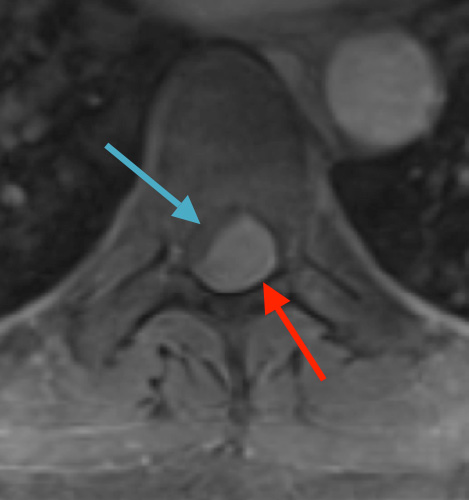

Postoperative MRI T1w demonstrating interval resection with cord re-expansion (blue arrow)

Postoperative MRI T1w demonstrating a gross total resection